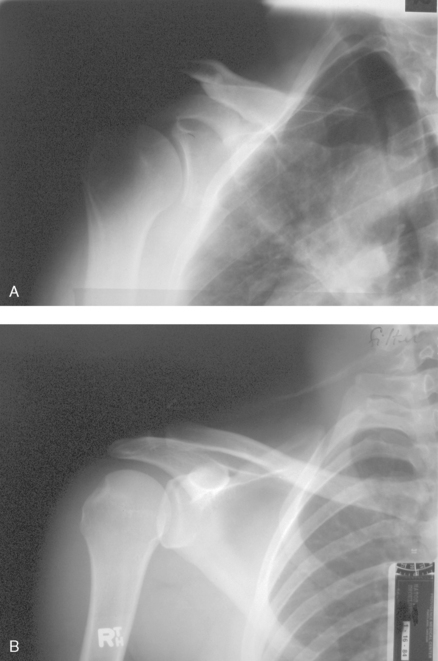

Structures shown: The image shows the bony and soft structures of the shoulder and proximal humerus in the anatomic position (Figs. 5-14 to 5-16). The scapulohumeral joint relationship is seen.

Fig. 5-14 A, AP shoulder, external rotation humerus: greater tubercle in profile (arrow). B, AP shoulder, neutral rotation humerus: greater tubercle (arrow).

Fig. 5-15 AP shoulder, internal rotation humerus: greater tubercle (arrow); lesser tubercle in profile (arrowhead).

Fig. 5-16 A, AP oblique projection of right shoulder without use of compensating filter. B, AP projection of same patient with compensating filter. Note improvement of visualization of bony and soft tissue areas with filter.

External rotation: The greater tubercle of the humerus and the site of insertion of the supraspinatus tendon are visualized (see Fig. 5-14, A).

Neutral rotation: The posterior part of the supraspinatus insertion, which sometimes profiles small calcific deposits not otherwise visualized (see Fig. 5-14, B), is seen.

Internal rotation: The proximal humerus is seen in a true lateral position. When the arm can be abducted enough to clear the lesser tubercle of the head of the scapula, a profile image of the site of the insertion of the subscapular tendon is seen (see Fig. 5-15).